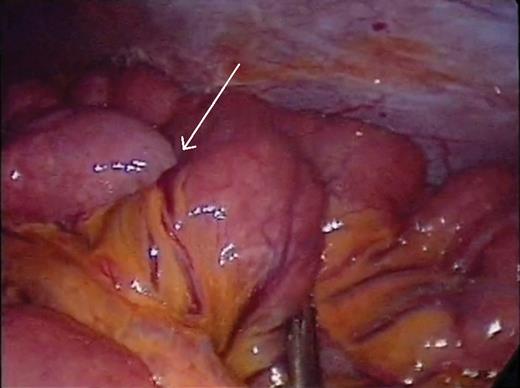

A 41-year-old female presented with 3 weeks of intermittent crampy epigastric abdominal pain, nausea and diarrhea. She was able to tolerate a liquid diet but not solids. She had one episode of vomiting and lost 6 lbs over the course of 3 weeks. Her vital signs, physical examination and laboratory studies were unremarkable. She did not have a history of prior abdominal surgery or malignancy. A CT scan demonstrated two areas of small bowel intussusception (Fig. 1A and B), without evidence of bowel obstruction or mass. The patient underwent exploratory laparoscopy using a 5 mm 30° camera and two 5 mm working ports. Six separate regions of intussusception within the small bowel were discovered between 55 and 130 cm from the ligament of Treitz. All areas of intussusception were short and witnessed to undergo spontaneously reduction (Fig. 2A and B), except for one (Fig. 3), which was resected through a mini-laparotomy. There was no obvious evidence of masses, adhesions or serosal abnormalities along the small bowel. There were prominent lymph nodes noted in the small bowel mesentery (Fig. 4). The postoperative course was uneventful and she was discharged 4 days after her operation. She had resolution of symptoms and had no recurrence after 3 years of follow-up. Pathologic examination of the small bowel demonstrated no evidence of malignancy, lead point, pathologic changes or sprue. Likewise, there was no evidence of acid-fast organisms, fungal or helminth parts identified. The enlarged mesenteric lymph nodes demonstrated reactive follicular hyperplasia and multifocal non-necrotizing lipogranulomas.

(a) Short segment of small bowel intussusception (arrow) that reduced spontaneously during laparoscopy. (b) A separate segment of small bowel intermittently intussuscepting and reducing (arrow) during laparoscopy.